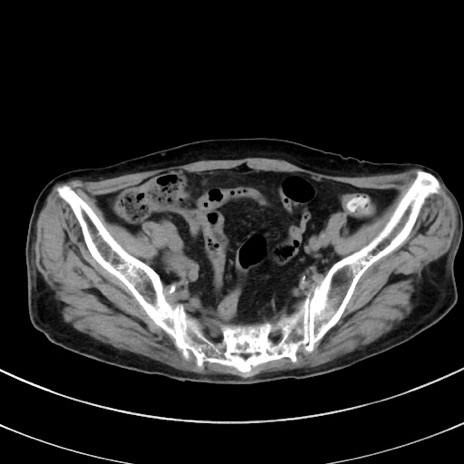

症例33(横断像)

【症例】70歳代 女性

【主訴】心窩部痛

【現病歴】延髄病変の精査・加療にて神経内科入院中。本日より心窩部痛あり。

【既往歴】虫垂炎

【身体所見】右下腹部を中心に圧痛と反跳痛あり。

【データ】WBC 10900、CRP 0.02